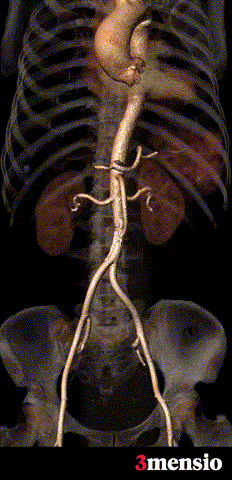

入路血管走形良好,零星附壁钙化,内径可,整体入路血管条件良好

入路钙化概览

入路概览